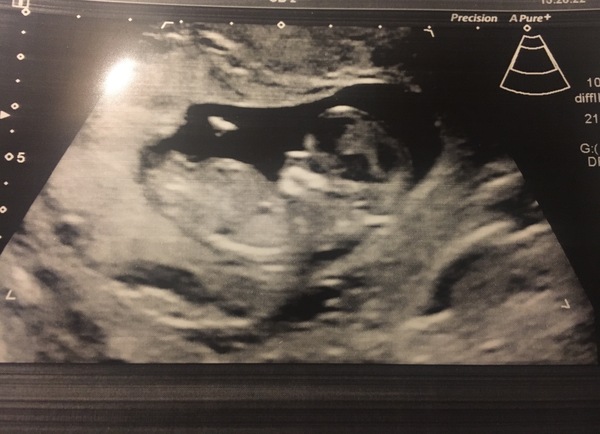

Thought I'd just share this with you lovely ladies. My dates are 8+6, measuring 9 so not bad. Saw and heard the heart beat. Was in tears all the way through, so happy. Finally feels real and like the nausea is worth it to see the little bean. It was even doing a little waggle dance inside which made me laugh!! Got some lovely pics too. This is our favourite as it shows the heart beat. Nice and strong. Just what we needed to see before Christmas!